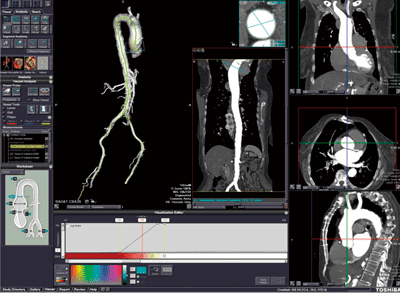

■TAVRのソリューション

“CT TAVR Analysis”アプリケーションは,近年,わが国においても保険適用の可能性が示され,今後大きく発展していくことが予想されるTAVRの術前検討のサポートを目的としている。大動脈弓周辺から腸骨動脈周辺まで造影されたCT画像を読み込むと,大動脈・腸骨動脈セグメンテーション,左右腸骨動脈別の芯線トラッキング,および壁輪郭抽出が自動で行われる。自動抽出された動脈の情報を基に,術前検討のために必要な大動脈弁輪径,ST-junction径,および左右の腸骨動脈径等,各種パラメータを簡便に計測することができ(図4),置換する人工弁の選択や,カテーテルのアクセスルートの確認などに活用することができる。解析した結果は,CT TAVR Analysis専用のレポートとして残すことができる。ほかのアプリケーションと同様に,各種統計情報は自動的にレポートに引き継がれる。

図4 CT TAVR Analysis解析例

(画像ご提供:Stony Brook病院様)